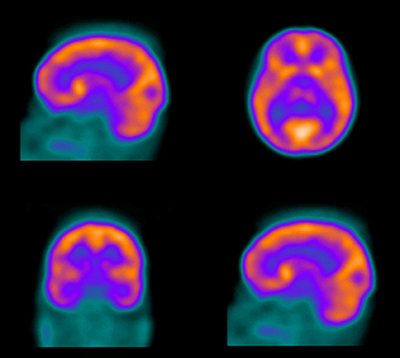

The Section of Nuclear Medicine of the Department of Radiology at Wake Forest University School of Medicine offers an ACGME-accredited one-year fellowship program in nuclear radiology. The training program includes classroom time, training and experience in nuclear medicine, nuclear cardiology, positron emission tomography (PET/CT), as well as in theranostics (therapy plus diagnostics).

The fellowship is designed to provide the trainees an in-depth experience in all areas of clinical nuclear medicine, both diagnostic and therapeutic. The fellow is taught the basic principles upon which the field of nuclear medicine is founded, including: